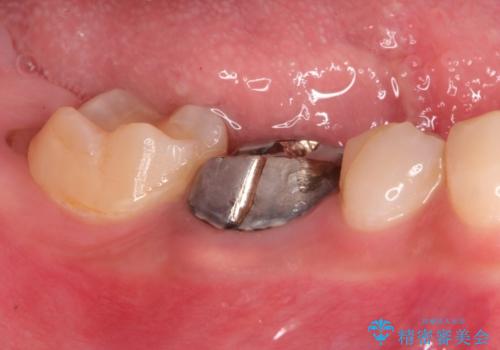

- 奥歯がズーンと痛いことを主訴に来院されました。

根管治療時に穿孔部位を認め、MTAにて修復し、分岐部の歯周ポケットおよび骨欠損に対しては、再生治療を行うことで、正常な歯周状態の獲得ができました。

歯冠修復はオールセラミッククラウンで行なっております。